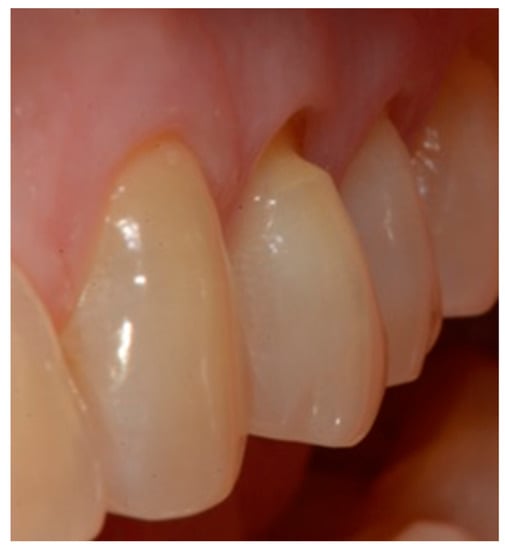

- Selection of the shades (dentinal masses and enamel) of the tooth to be restored (Figure 1);

- Initial measurement of the length of the clinical dental crown (performed with a millimeter periodontal probe placed adjacent to the dental crown and having as a reference the most apical part of the gingival sulcus and the highest part of the crown) and photography of the lesions at time 0 (t0) (Figure 2a).